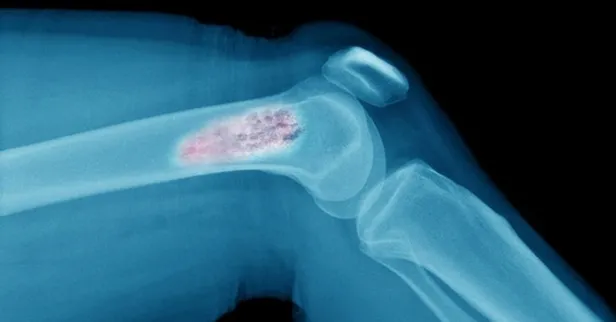

Kemik iliği kanseri, ilik içerisinde yer alan hücrelerin anormal bir şekilde bölünmesi, dolayısıyla da sayılarını artırmasına bağlı olarak ortaya çıkar. Lösemi ve lenfoma da kemik iliğindeki hücrelerin artışıyla meydana gelen kanserler olmakla beraber, en sık görülen kemik iliği kanseri multipl miyelomdur.

Multipl Miyelom, asıl görevi vücuda giren mikroorganizmaları tanımak ve bu mikroorganizmaların etkisiz hale getirilmesini sağlayan antikorları üretmek olan plazma hücrelerindeki anormal artışla karakterize bir kanserdir.